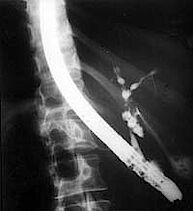

Nach der Prämedikation schluckt der Patient ein Seitblickendoskop, welches nach Passage von Speiseröhre und Magen im Zwölffingerdarm platziert wird. Dann wird die Papille (Einmündungsstelle) von Gallengang und Bauchspeicheldrüsengang betrachtet und unter Sicht sondiert. Über diese Sonde wird Röntgenkontrastmittel in das Gallengangsystem eingespritzt, um die Veränderungen der Gallenwege mit Hilfe der Röntgenbilder sichtbar zu machen. Sind für den Ballonkatheter erreichbare Gallengangsengstellen auf den Röntgenbilder erkennbar, kann eine Ballondilatation vorgenommen werden. Um zu den Engstellen zu gelangen, wird die Gallengangseinmündung im Zwölffingerdarm durch Schneidekatheter eröffnet (Papillotomie). Mit Hilfe eines Katheters wird ein dünner weicher Draht über die Stenose geschoben. Dieser Draht ist die Leitschiene für den Ballonkatheter, der auch über die Stenose geführt wird [Abb. 2 u. 6]. Die Aufdehnung der Engstelle mit dem Ballon wird für einige Minuten vorgenommen. Im Fall einer engen Gallengangsanastomose werden zusätzlich, nach dem Rückzug des Ballonkatheters, Gallengangs- Stents über die dilatierte Engstelle geschoben. Die Gesamtdauer des Eingriffs kann bis über eine Stunde betragen.